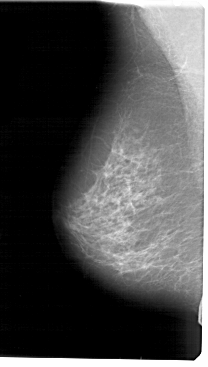

A_1458_1.RIGHT_CC

RIGHT_CC LINES 4861 PIXELS_PER_LINE 2656 BITS_PER_PIXEL 12 RESOLUTION 43.5 OVERLAY

FILE: A_1458_1.RIGHT_CC.OVERLAY

TOTAL_ABNORMALITIES 1

ABNORMALITY 1

LESION_TYPE CALCIFICATION TYPE PLEOMORPHIC DISTRIBUTION CLUSTERED

ASSESSMENT 4

SUBTLETY 3

PATHOLOGY BENIGN

TOTAL_OUTLINES 1

BOUNDARY